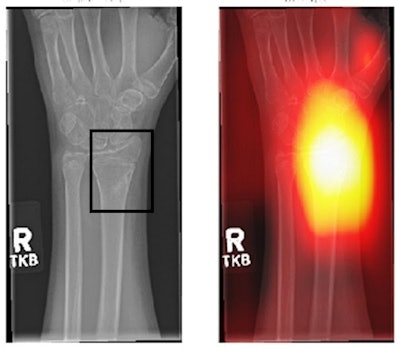

(Left) Area with fracture (in the box). This may not be easily picked up by an inexperienced radiographer. (Right) An AI-generated heatmap, directing the radiographer to check the area. Figure courtesy of Clare Rainey and MURA dataset.The survey highlights issues with the perceptions of reporting radiographers in the U.K. regarding the use of AI for image interpretation, according to Rainey.